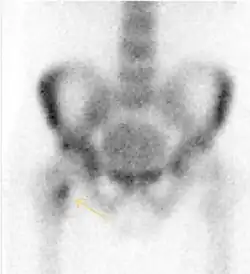

Figure 8:

-

X-ray of a patient with transient osteoporosis of the left hip showing osteoporosis.[1] -

Coronal stir imaging in transient osteoporosis, showing diffuse edema.[1] -

Scintigraphy (A), sagittal T1 (B), and coronal PD fat sat of a patient with a subchondral fracture of the femoral head with convex shape to the articular surface.[1] -

Coronal T1 of a patient with avascular necrosis of the femoral head.[1]